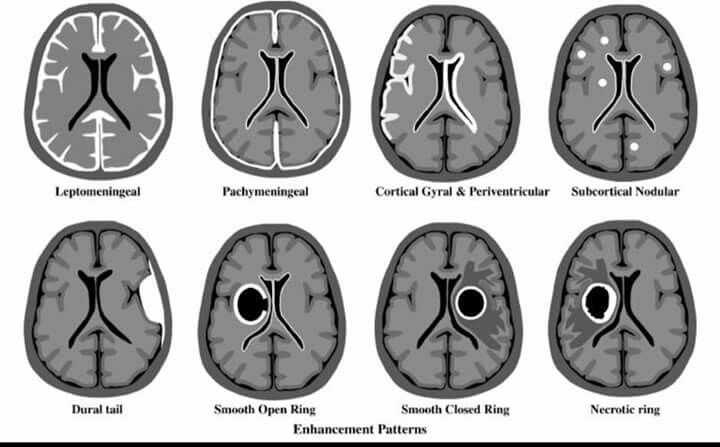

From our half-day #morningcase: Differentiating lepto and pachymeningeal enhancement can be tricky. Here is a figure that may be helpful (ref: https://t.co/JqRm8X3aT3) #medtwitter #neurotwitter